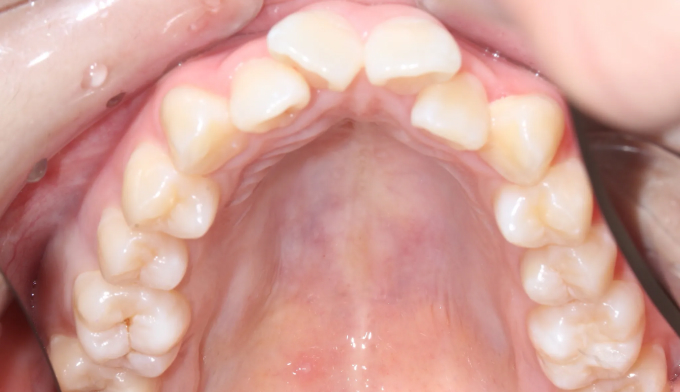

덧니

덧니가 생길정도로 공간이 부족한 경우, 발치교정이 대표적인 방법 중 하나입니다.

하지만 그 필요한 공간의 정도와 안모를 종합적으로 고려하였을때, 비발치로도 충분히 가능한 경우가 많습니다.

이번 케이스도 필요한 공간이 많긴 하지만, 입의 보양이나 각도를 고려하였을 때 비발치로 교정 가능한 경우라 판단되어 발치없이 성공적으로 치아를 배열하였습니다.

총 교정기간은 15개월입니다.